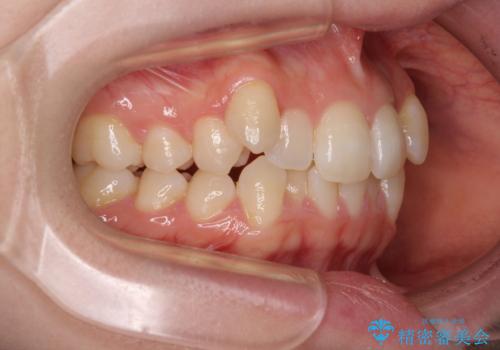

- 八重歯が気になるとのことで来院された患者様です。

上顎前歯部はデコボコが強く、歯を並べるためのスペースが不足しているため、左右の第一小臼歯を抜歯することとしました。

また、抜歯して確保したスペースが不足してしまうのを防ぐため、補助装置を併用しています。

矯正治療の前に上下左右の親知らずの抜歯も行いました。